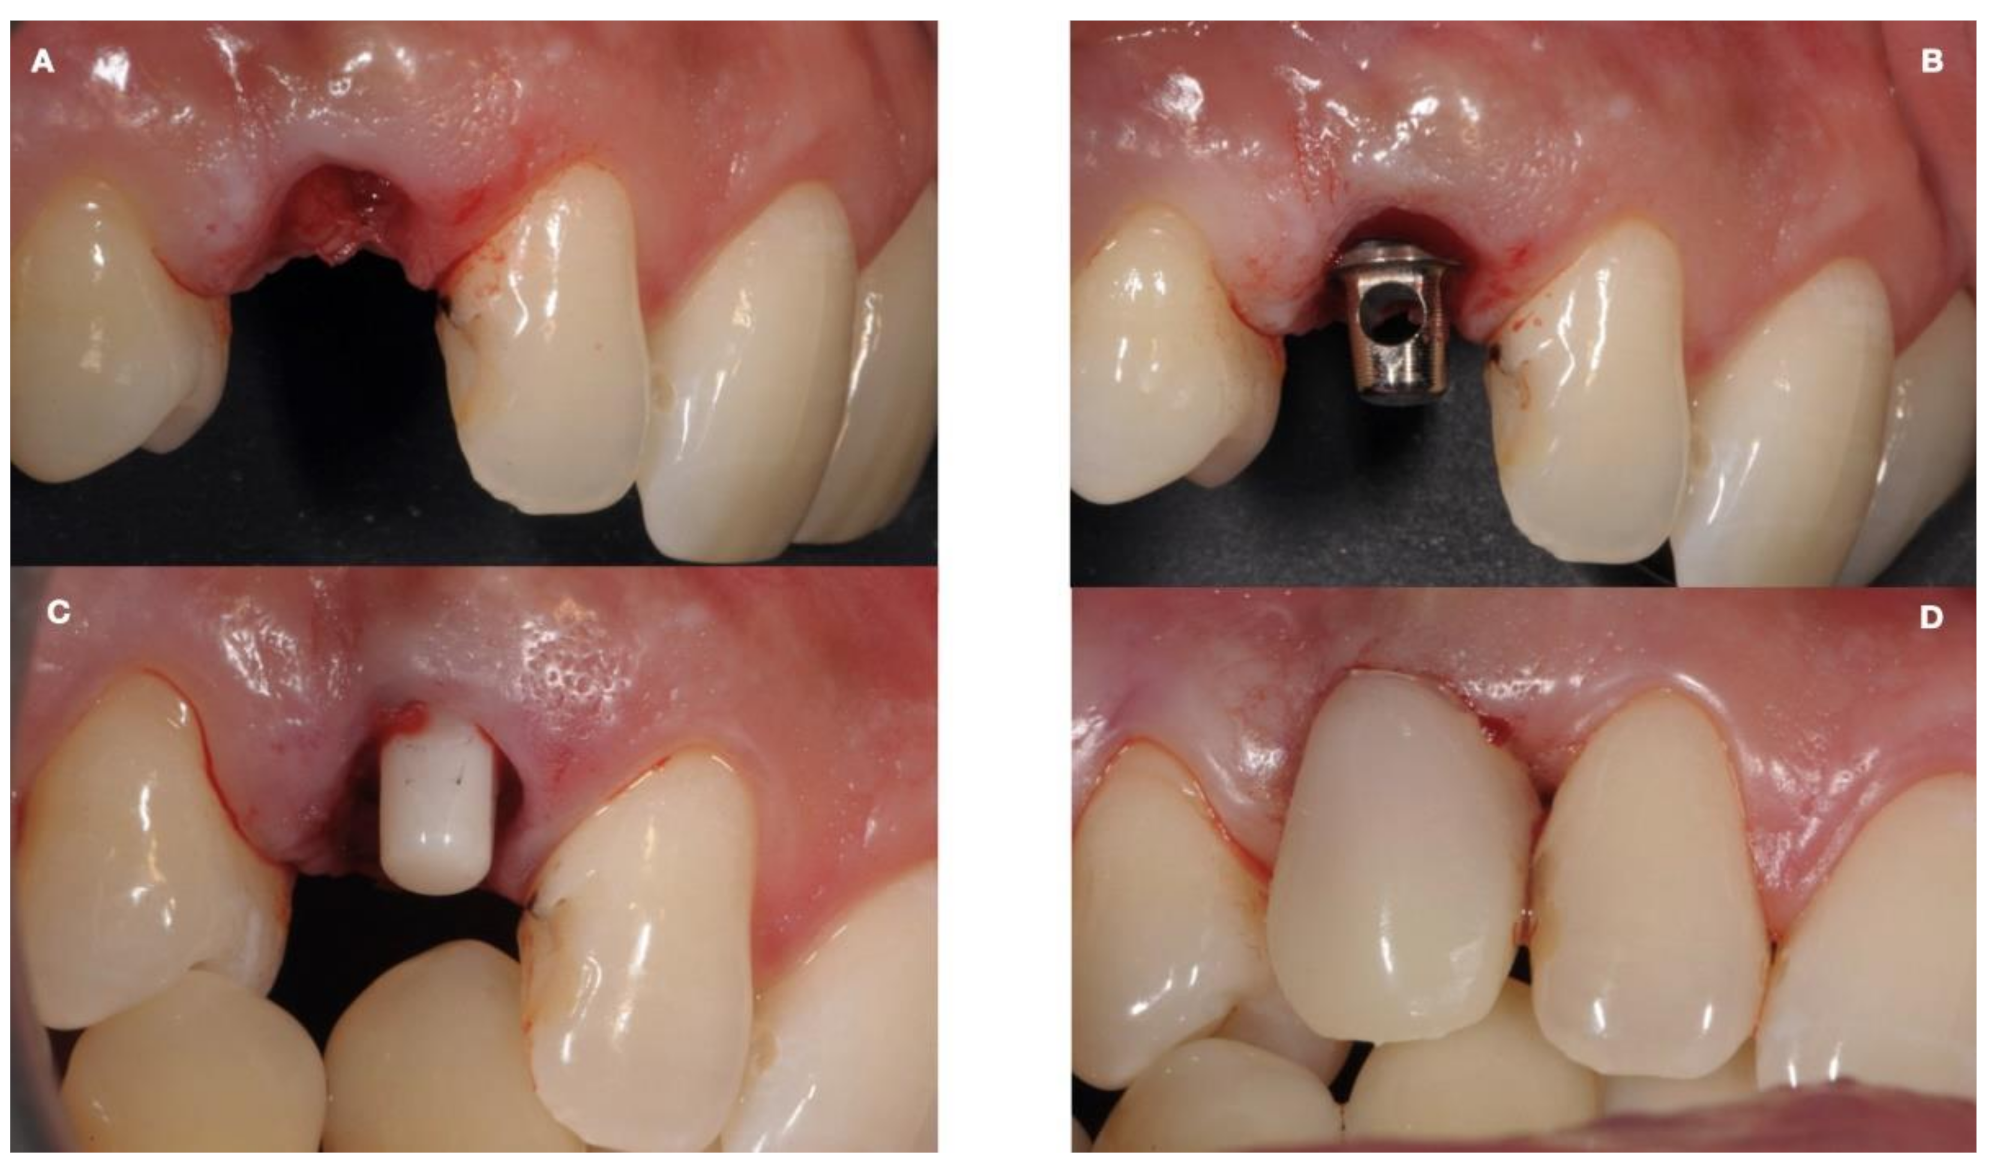

| (a) Surgical removal of the deciduous tooth and orthodontic extrusion, and taking in occlusion of the permanent canine |

| (d) Removal of the deciduous tooth and replacement with implant-borne-prosthesis living in situ with the impacted canine, accepting the compromise of involving the impacted tooth in the implant seating procedure |

| (e) Surgical removal of the impacted canine and, in a second stage, removal of the deciduous tooth and replacement with implant-borne-prosthesis |